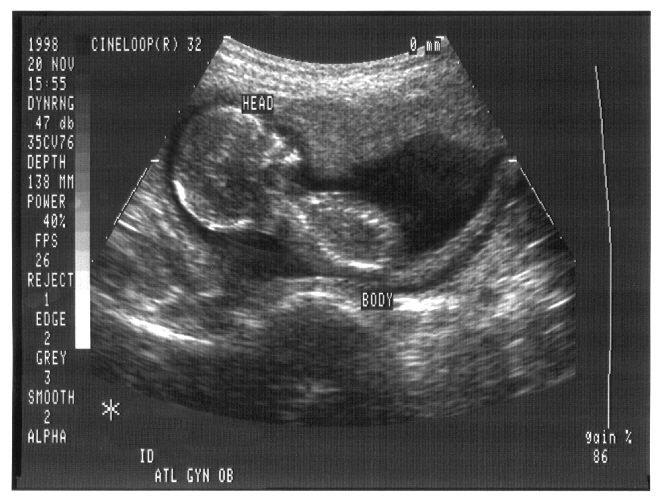

A Sociedade Portuguesa de Ecografia Médica (SPEM) manifestou-se hoje contra as chamadas "ecografias emocionais" feitas fora do âmbito médico, considerando que expõem grávidas e fetos a tempos excessivos de exposição a ultrassons, o que pode ter efeitos nocivos.

Francisco Gaivão explicou que estas ecografias não são realizadas por médicos, usam tecnologia 4D, em não se vê o feto por dentro, mas apenas por fora, "que é o que a família quer ver".